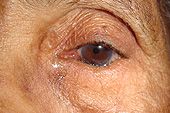

Patient with entropion left lower lid (lashes and lid rolled in). This causes chronic pain, blurred vision, tearing, redness, and eventually, corneal scarring in the eye

Immediately after repair of entropion. Note that the lid and lashes are in better anatomic position

Close-up, entropion

Close-up, after repair